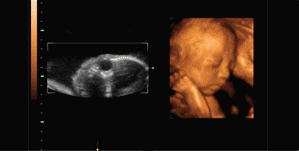

误区一:四维彩超是彩色的?四维彩超是目前世界上最先进的彩色超声设备,是在三维超声图像的基础上加上时间维度参数,从而更直观更清晰地呈现胎儿在宫内的动态图像,所以,有时也被称作实时三维。

通俗地说,三维彩超是单张图片,四维彩超近乎录像,其两者画面都是黑白色或黄土色,只不过四维彩超可以让孕妈妈看到胎宝宝一连串的动作,这让不懂超声医学的孕妈妈感到亲切、直观。